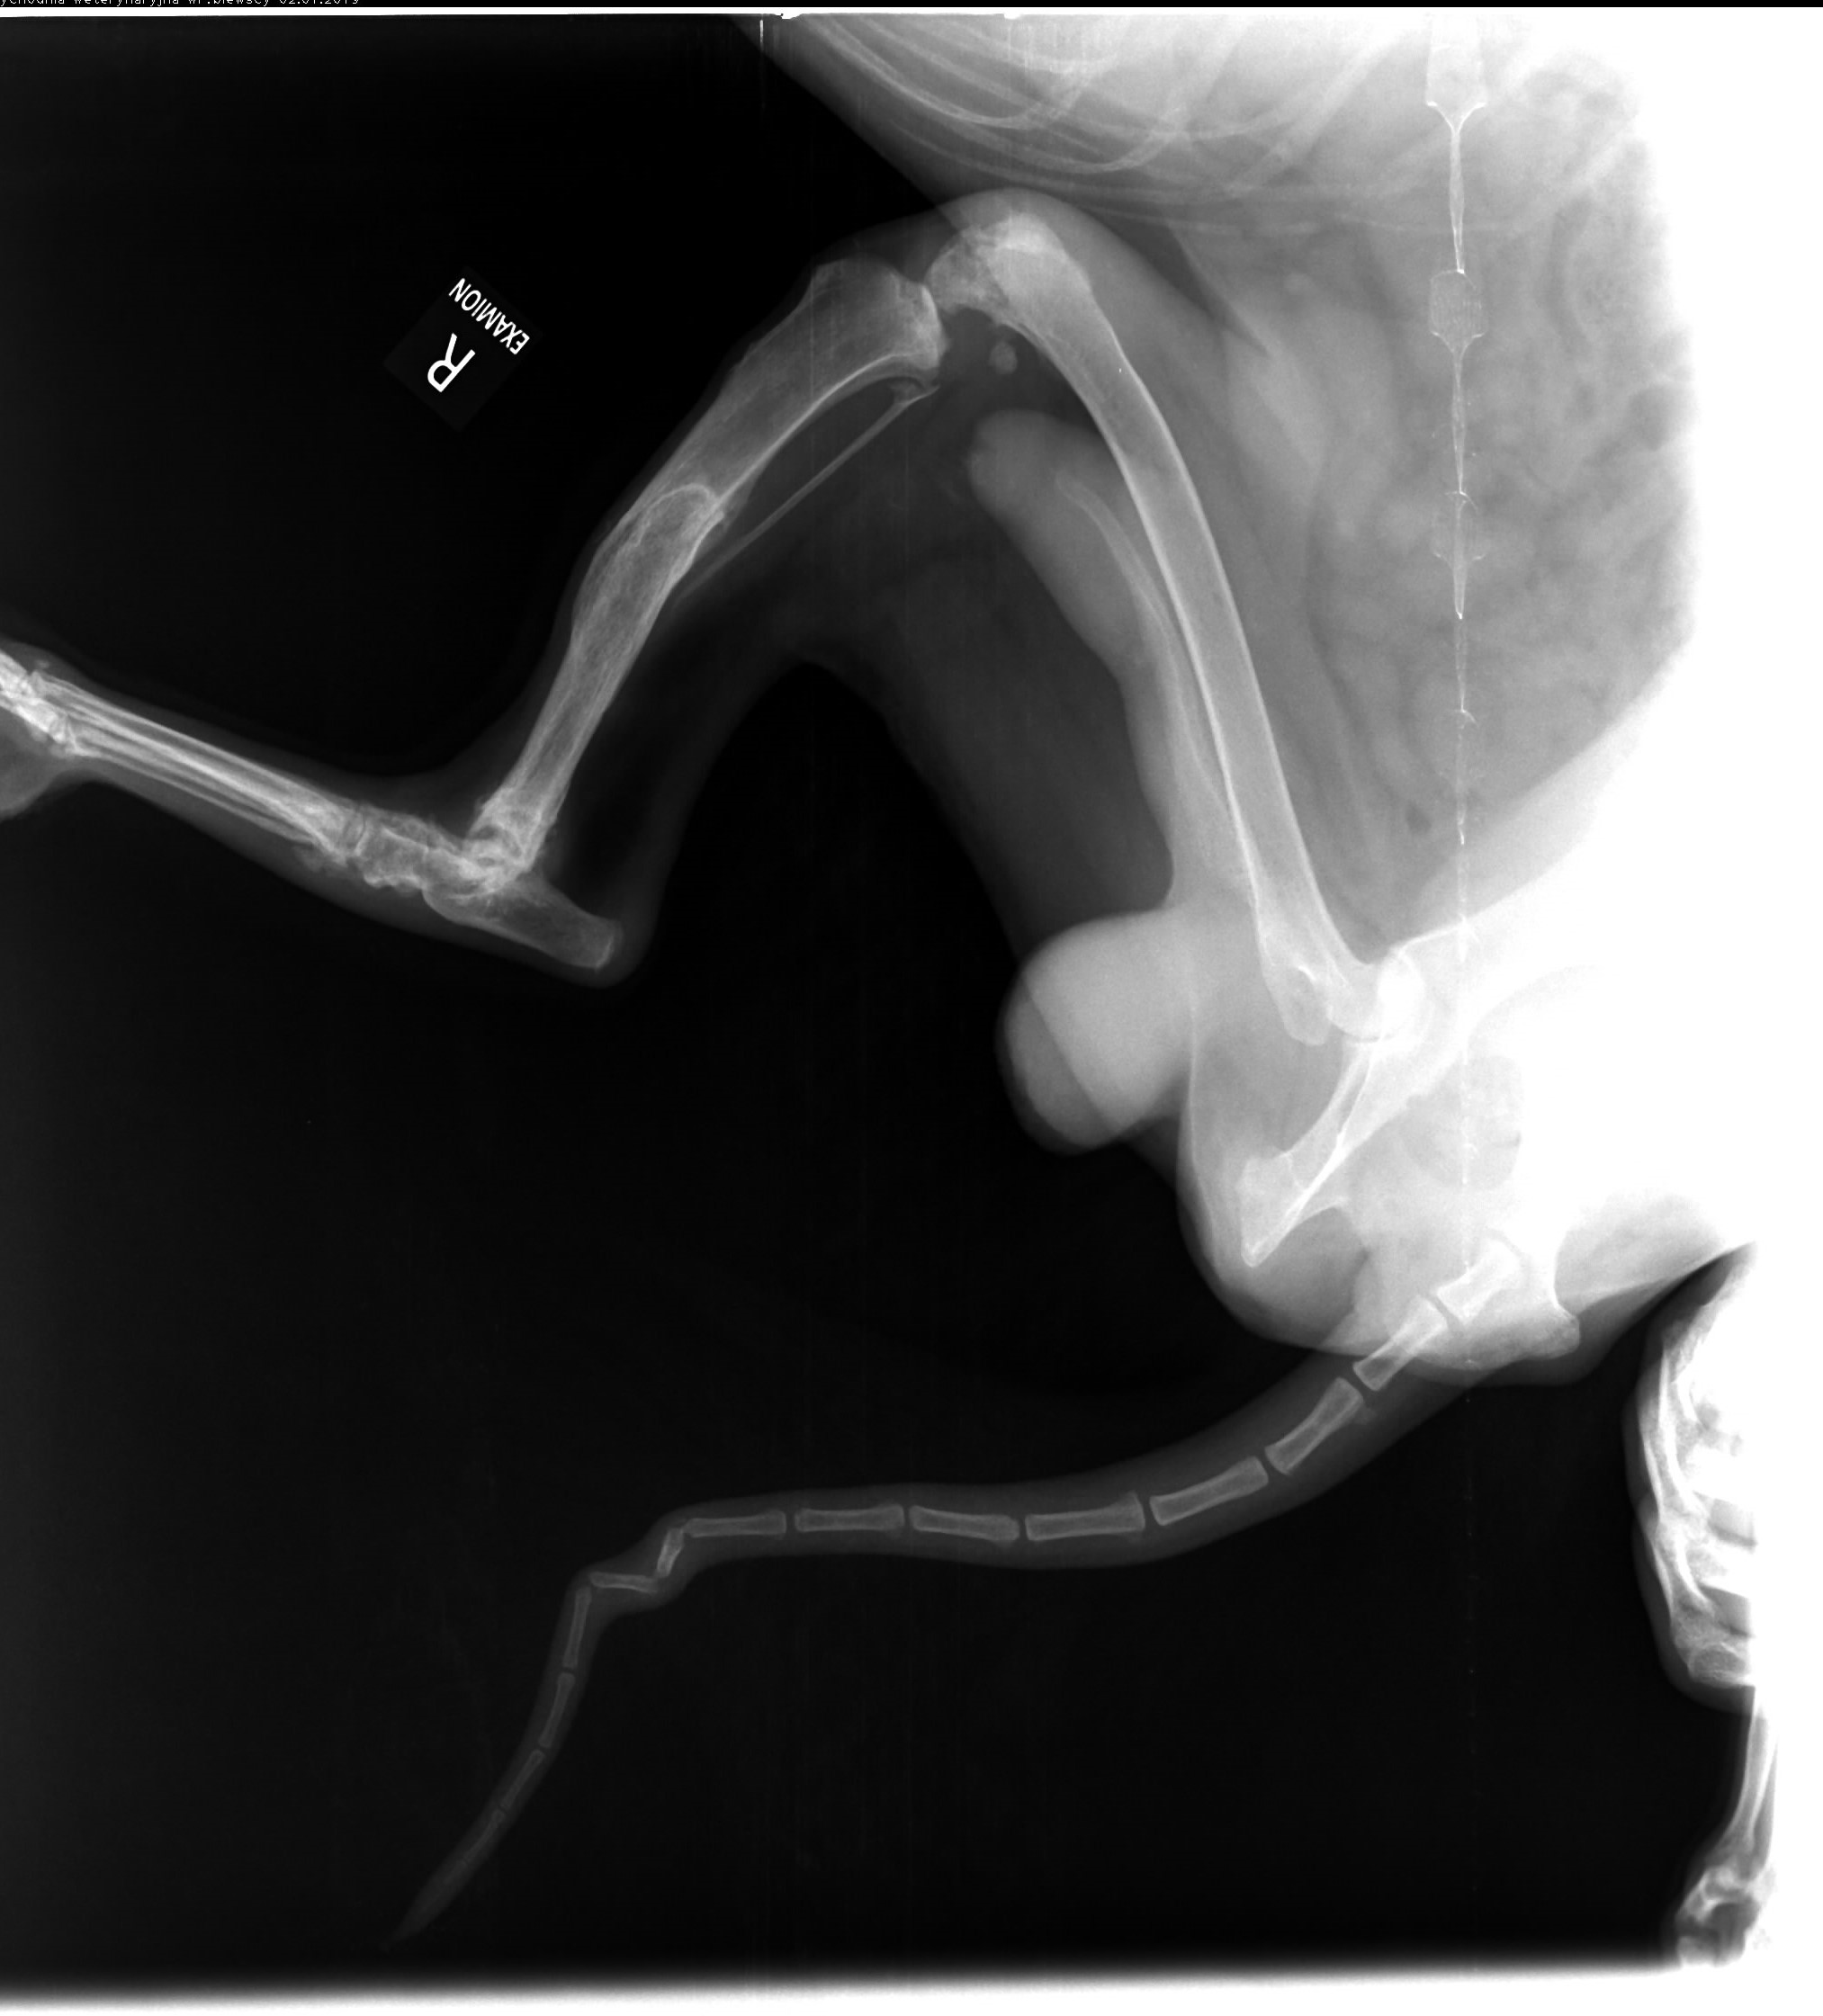

Leoś przebywał długie lata w schronisku w Raciborzu. Nikt Leosia nie chciał adoptować , taki był wycofany , bał się ludzi a w szczególności mężczyzn , co sami na sobie odczuliśmy jeżdżąc na wizyty zapoznawcze do hotelu w Gliwicach gdzie został przetransportowany. Leoś skradł nasze serca. Pomimo nie małych wątpliwości podjęliśmy decyzję o adopcji Leona i to była najlepsza decyzja. Leoś to piesek o wspaniałym charakterze , zrobił bardzo duże postępy , bez nas nigdzie się nie ruszy. Jesteśmy zmuszeni prosi o pomoc. Niestety okazało się , że nasz pupil zaczął mieć problemy z chodzeniem. Diagnoza lekarska była jednoznaczna, bez operacji Leoś przestanie chodzić. A opis lekarza ortopedy brzmiał tak : CAŁKOWITE ZWICHNIĘCIE STAWÓW NADGARSTKOWYCH , CAŁKOWITE ZERWANIE WIĄZADEŁ , DAWNE ZŁAMANIE KOŚCI PISZCZELOWEJ Z NIEPRAWIDŁOWYM ZROSTEM. LICZNE ZWYRODNIENIA STAWÓW, Załączam zdjęcia RTG .

Obecnie Leoś jest po operacji łapy przedniej lewej co ilustrują zdjęcia.

Dzis Leos jest już po operacji drugiej przedniej łapki. Wszystkim i z osobna dziękujemy za wsparcie. Podczas wizyty okazało się, że Leos musi mieć operacje na dwie tylne łapki. Koszt operacji to około 2500zl. Załączam opis ortopedy.